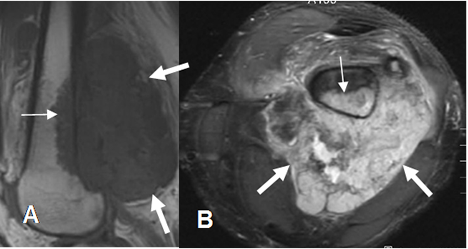

Fig 8. Señal anormal en STIR.

A: RM sagital en T1. Lesión hipointensa en la parte posterior del fémur (Flecha delgada), con gran masa infiltrativa de tejidos blandos, (Flecha gruesa) que corresponde a osteosarcoma.

B: RM axial en STIR. Tanto la lesión osea como de tejidos blandos, son hiperintensas en relación con la grasa, indicando patología.